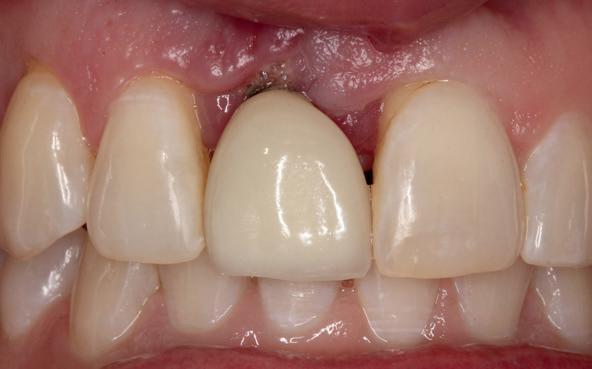

Implantologische behandelingen in het esthetische front vragen meer dan technische vaardigheid alleen. Ze vragen om overzicht, timing, vertrouwen en een team dat als vanzelf samenwerkt onder druk. Juist bij complexe casussen, waarin angst, infectie en hoge esthetische verwachtingen samenkomen, wordt zichtbaar hoe bepalend de rol van de tandartsassistent is.

Deze casus beschrijft een uitgebreide immediate implantaatbehandeling bij een patiënt die door meerdere collega’s werd geweigerd. Niet omdat de mogelijkheden ontbraken, maar omdat de complexiteit vroeg om een perfect afgestemde samenwerking. Het verhaal laat zien hoe de assistent in zo’n traject veel meer is dan een uitvoerende kracht of “mal”, maar een dynamische surgical guide die het proces mede stuurt, bewaakt en mogelijk maakt.De patiënt: wanneer alles samenkomt

De kern van haar vraag was eenvoudig en tegelijkertijd uitdagend: Is het mogelijk om mijn huidige brug te dupliceren en een nieuwe brug te vervaardigen met minder complicaties?

Na het klinische onderzoek volgde het röntgenologisch traject. De CBCT liet precies zien wat we al vreesden: een front waarin het bot onregelmatig was, duidelijke radiolucenties rond de pijlers en een infectiegebied dat zich onder vrijwel de gehele brug had verspreid. Tegelijkertijd was er ook potentie. Net voldoende botstructuur om immediate implantaatplaatsing te overwegen, mits alles perfect gepland zou worden.